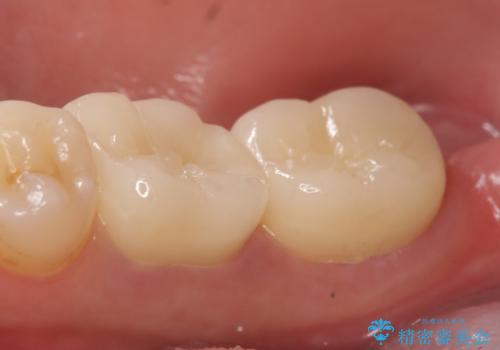

- 奥歯が欠けてしまったので診て欲しいといらっしゃった方の症例です。

再根管治療終了後、オールセラミッククラウンによる補綴を行いました。

今回用いたオールセラミッククラウンはジルコニアフレームという白い素材の上にセラミックを盛っているため、審美性が非常に高いのが特徴です。

また、ジルコニアは人工ダイヤモンドの材料にも使われているほど高い強度を持っており、そのためオールセラミッククラウンは審美性だけでなく、奥歯やブリッジの補綴も可能とするクラウンです。